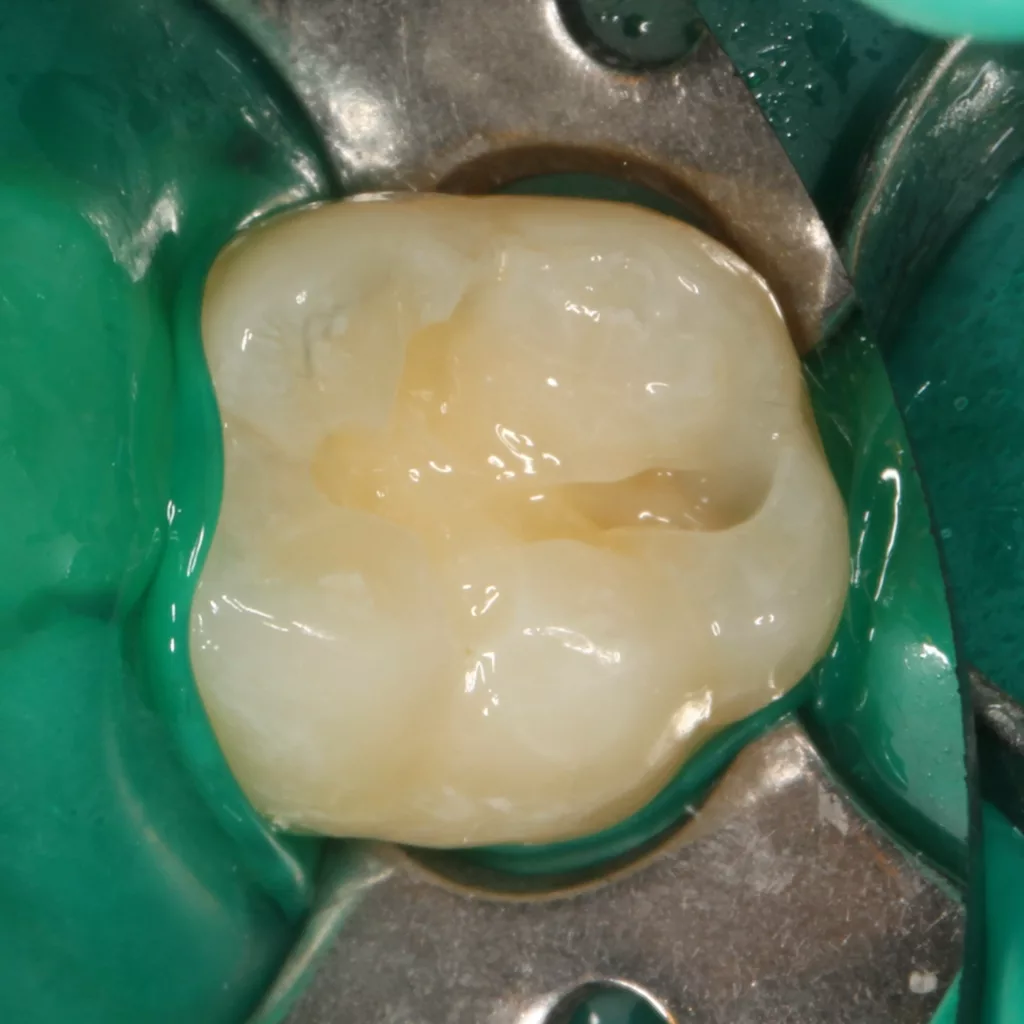

Fall 5: Versorgung einer okklusalen Kavität an einem unteren Molaren

Auch im Molarenbereich können Bulkflow-Materialien effektiv und ökonomisch eingesetzt werden, ohne Abstriche an der Ästhetik machen zu müssen, was der Fall des hier versorgten Zahnes 46 bei einer 22-jährigen Patientin zeigt. Die Abbildung 24 stellt die bereits präparierte und mit einem Einzelzahnkofferdam isolierte Kavität mit der Phosphorsäurekonditionierung der Schmelzränder (Gel Etchant, Kerr) dar. Die Entscheidung zur absoluten Trockenlegung fiel aufgrund der nicht so einfach kontrollierbaren Zunge und der vielen Schluckreflexe, was das Risiko einer ungewollten Speichelkontamination der Klebefläche unverhältnismäßig erhöhte.

Die Verwendung des Kofferdams ist generell eine sehr empfehlenswerte, aber keine zwingende Voraussetzung zur Etablierung einer suffizienten Kontaminationskontrolle [47,96]. Das bisher auch bereits verwendete Zwei-Schritt-Universaladhäsiv G2 Universal wurde hier in der selektiven Schmelzätztechnik angewendet, d.h., das Material arbeitet auf dem Dentin selbstkonditionierend (Abb. 25). Die bislang zu diesem innovativen Mehrflaschen-Universaladhäsiv publizierten Daten zeigen eine beeindruckende Performance, die den Vergleich mit sogenannten Goldstandards [98] wie einem Optibond FL nicht scheuen müssen [13,18,34,58,63,114,119,127,130]. Im nächsten Schritt wurden die einzelnen Höcker mit dem angenehm standfesten Flowable aufgebaut (Abb. 26). Die Abbildung 27 zeigt die komplett versorgte okklusale Kavität, die Abbildung 28 die Situation unmittelbar nach Ausarbeitung und Politur. Erneut beeindruckt die gute Farbadaptation.